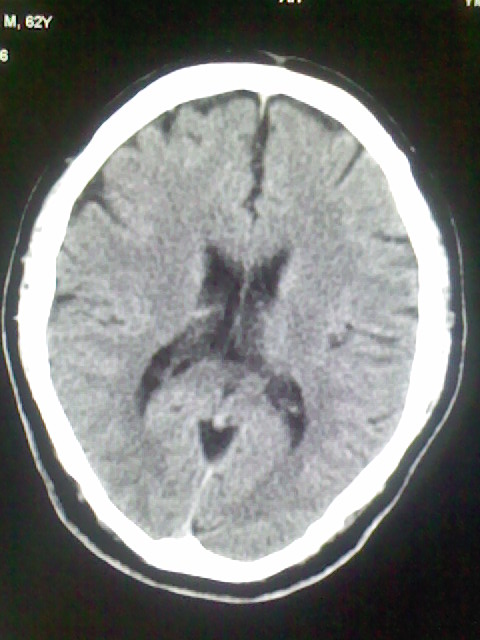

标题: CT15555:头痛 10余日 来诊大家帮忙看看 [打印本页]

标题: CT15555:头痛 10余日 来诊大家帮忙看看

脑萎缩

脑沟、裂增宽,提法脑萎缩,建议mt检查。

脑萎缩,以小脑为著。

脑沟、裂增宽,提示脑萎缩

老年脑

支持轻度脑萎缩。